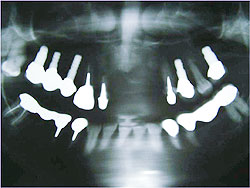

AQBは、結晶体の密度が高く純度も高いことが特長であり、三井記念病院におけるAQBインプラント症例では、最長18年を経過した臨床例においても、歯槽骨の状態は変わらず、逆に密になっていることが分かっている。そこで、上顎臼歯部の骨吸収症例において、サイナスリフトと同時にAQBインプラント1ピースを植立し、自家骨移植や人工骨移植を行わず、治療を行った症例を報告した。6例に施行し、全例、予後良好で、すべて植立後4ヵ月以内で咬合を開始した。GBR症例においてもAQBインプラント2ピースを埋入し、自家骨移植や人工骨移植は行わず、チタン入り非吸収性膜を用いたスペースメーキングを行った。その結果、4ヵ月後には歯槽骨の再生を確認した。

| AQBを用いて歯槽骨再生を図った症例 | |

GBR症例 ▼ ![]() 術前 ![]() 術直後 ![]() 膜除去直後 |